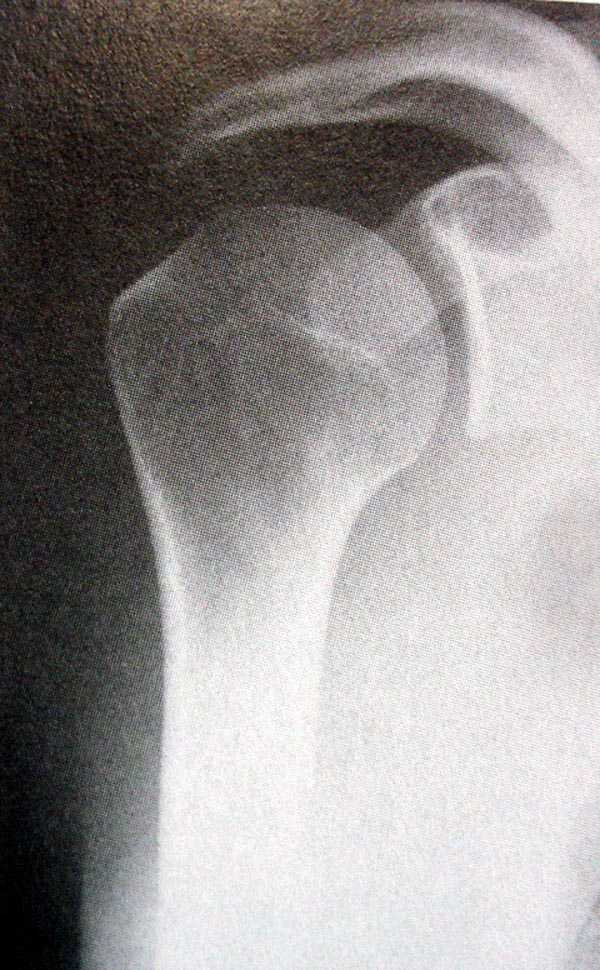

[Ortho] Закрытый оскольчатый перелом хир. шейки плеча со смещением

Рентгенологические исследования проксимального отдела плеча состоит

из прямого, бокового и аксиальных видов. Если имеются сложные

переломы тогда рекомендуется Томография, а так в большинстве случаев

достаточно бывает стандартных снимков.

Независимо от условий (нежелание рентгентехника или отсутствие

пленок) необходимо добиться рентгенограмм, особенно аксиальной,

потому что одна проекция не гарантирует, что не пропущен вывих в

плечевом суставе.

На выставленных снимках копии из книги: 1-2 прямая укладка и снимок;

3-3a боковой или Y;  4 аксиальная укладка и снимок.